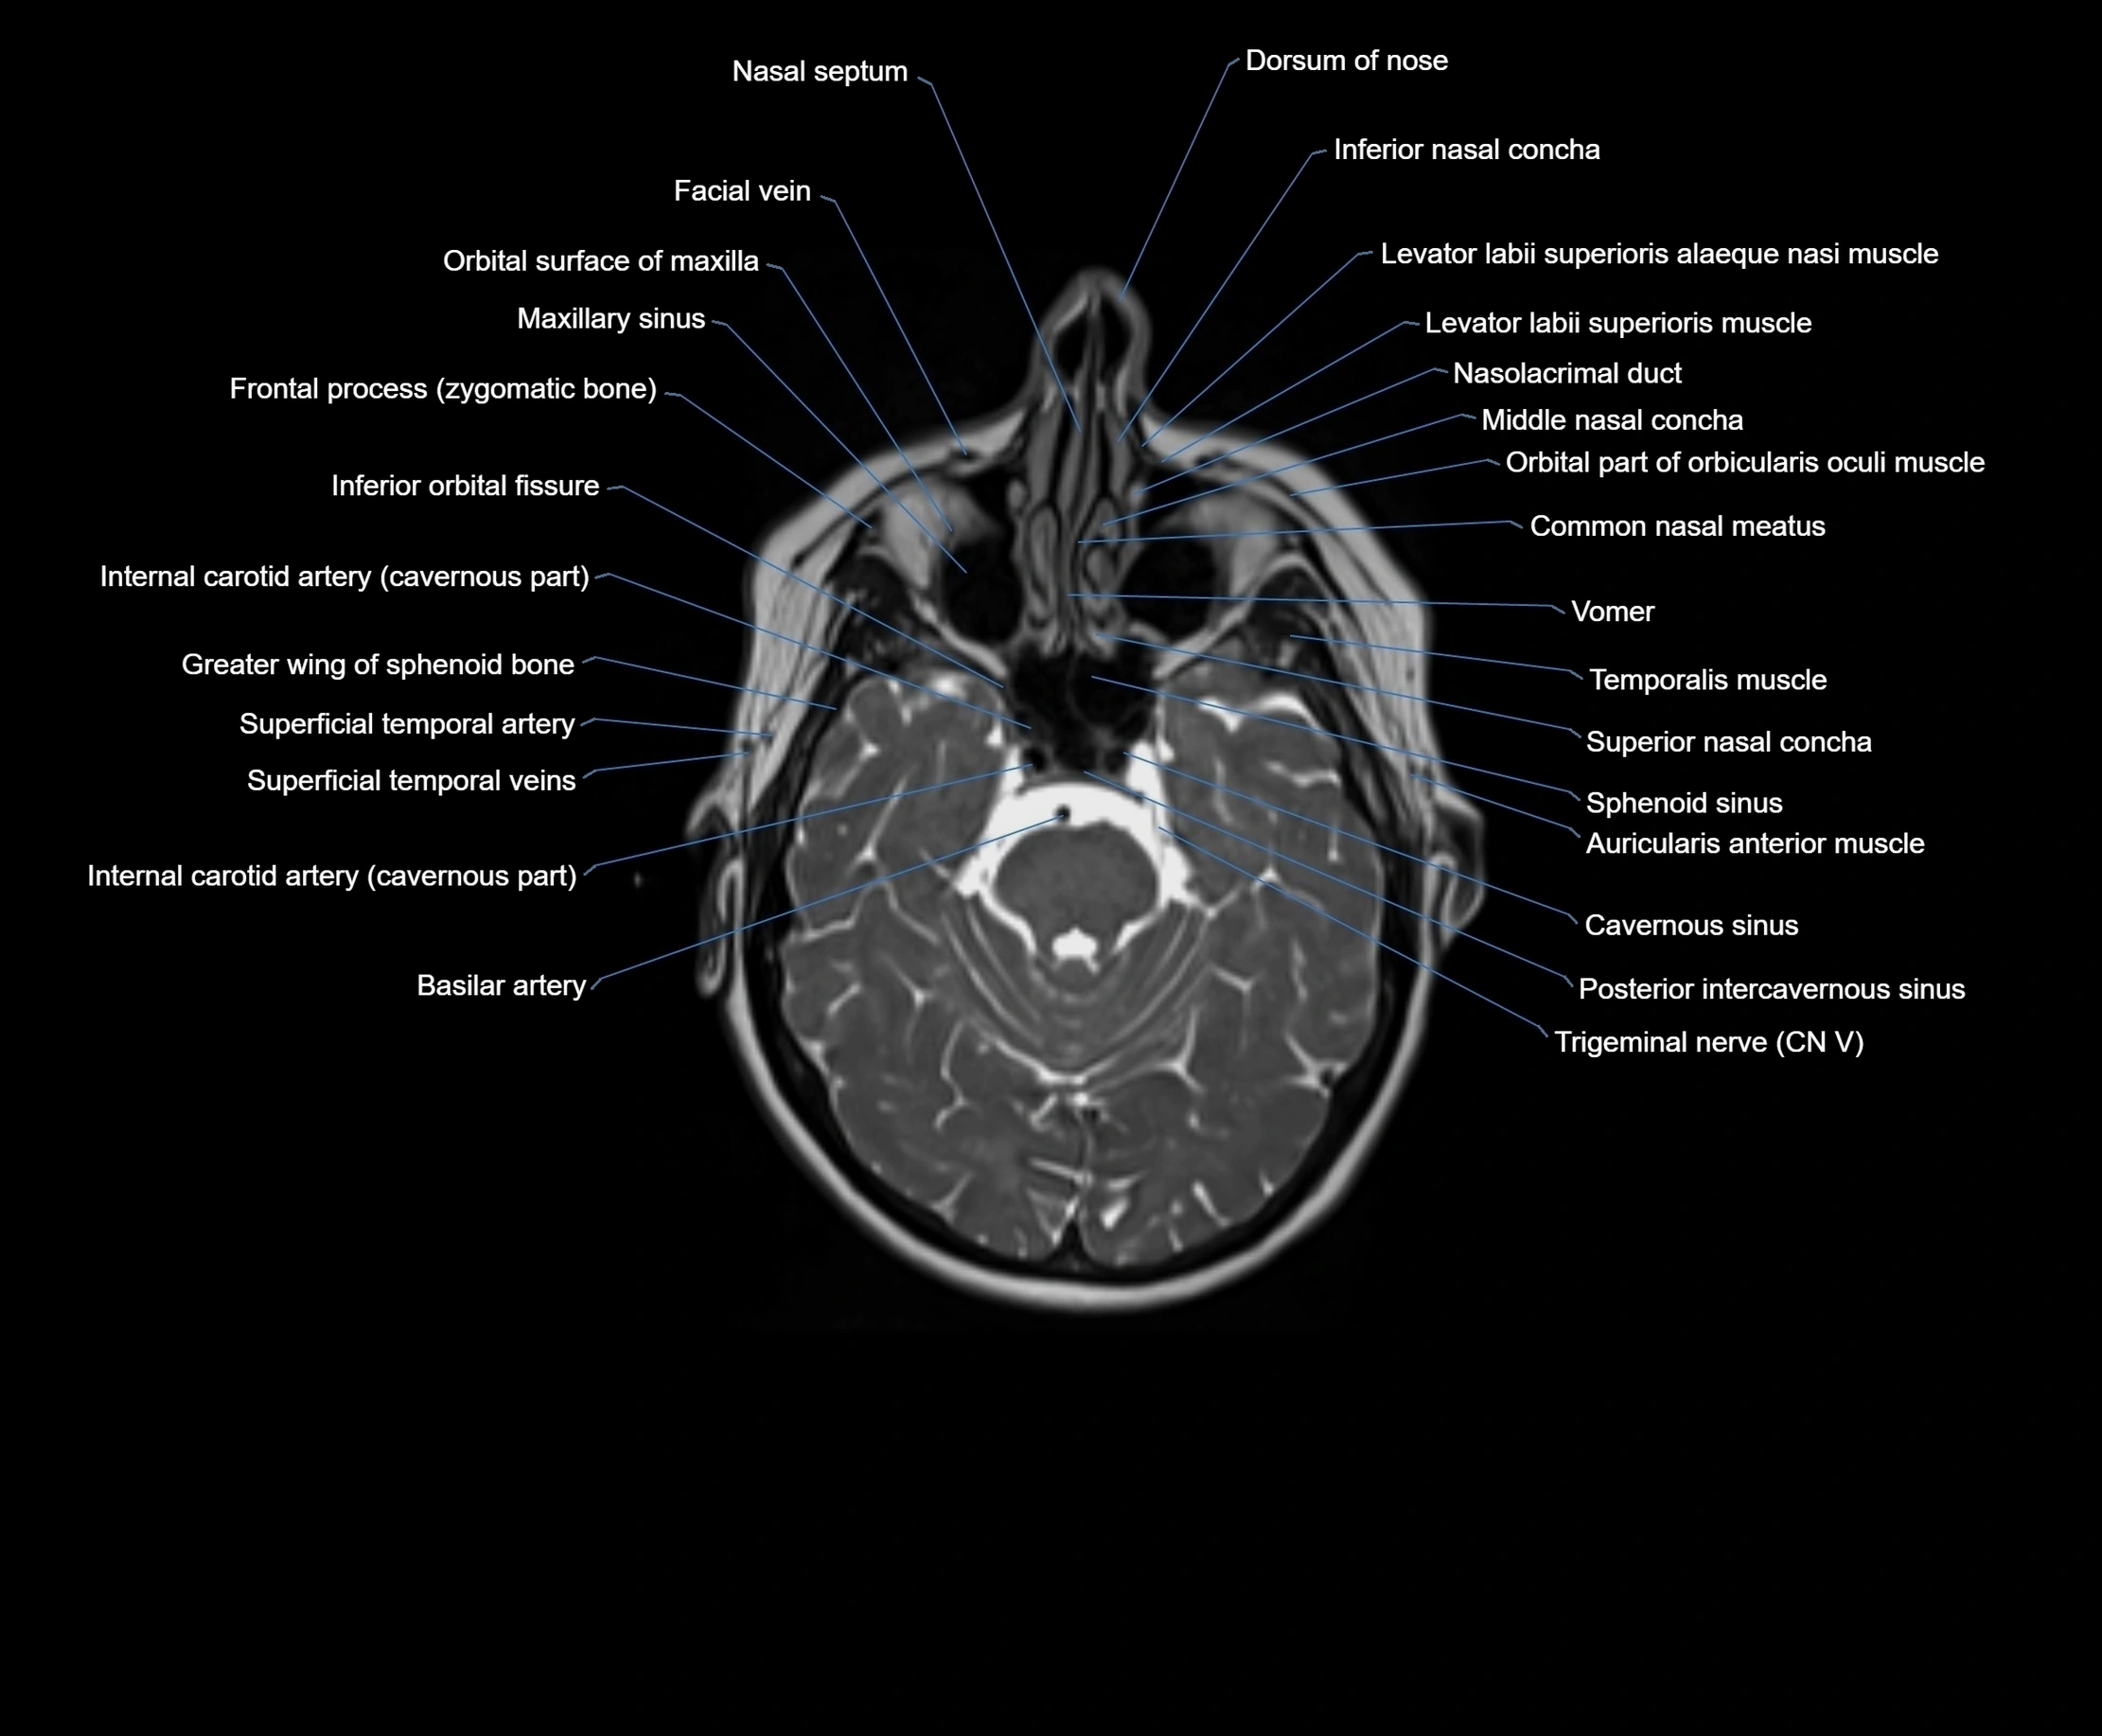

MRI images